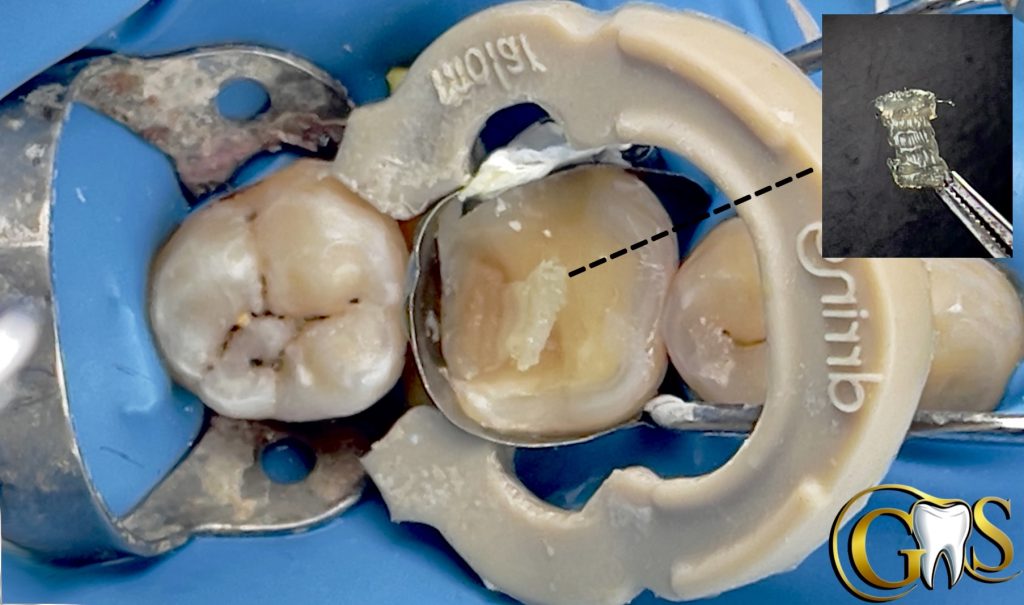

6-DWF (Decoupling with Fibers ) using Ribbond to improve Bonding with affected Dentine and for better stress Distribution

7-Ever X posterior for Dentine replacement (mimic Dentine under stresses)